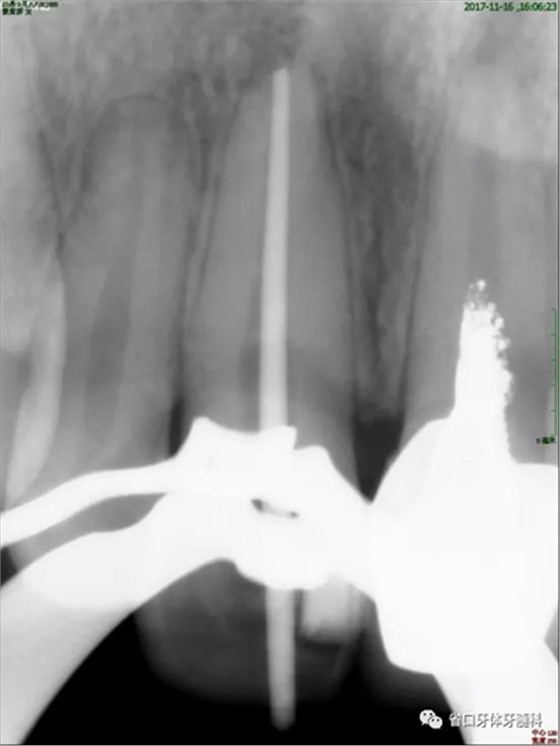

2周后復診:封藥存,患牙無不適,叩痛-,齦無紅腫。去封藥,清理根管,試主尖到位,沖洗、干燥,熱牙膠充填至釉牙骨質(zhì)界下2mm,照片顯示恰充。

圖4 試尖片